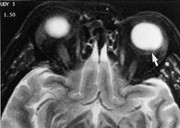

Melanomer gir karakteristisk signal fordi melanocyttene kan være paramagnetiske og gi høy signalintensitet på T1-vektede og lav signalintensitet på T2-vektede MR-bilder. Dette er karakteristisk, men mangler hos ca. 5 %. Postkontrast-T1-bilder med fettsuppresjon eller SPIR-teknikk er best egnet til å påvise små uveale melanomer (8) (fig 5).

Ekstraokulær utbredelse av uvealt melanom sees som et velavgrenset område med lav signalintensitet på T1-bilder, men med normal eller lav signalintensitet på T2-bilder i forhold til det orbitale fettet. Etter kontrast fremkommer bare moderat oppladning. MR er nyttig for å skille mellom en ekstraokulær ekspansjon og et ikke-oppladende fibrotisk arr i nær relasjon til sclera etter lokal stråleterapi.